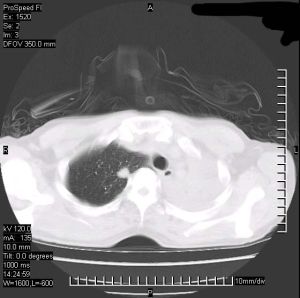

肺不張的CT圖像(1)一側或雙側肺不張:常由多種原因如胸肌膈肌麻痹咳嗽反射消失,及支氣管內分泌物梗阻等綜合而發生。一側或雙側的肺不張起病很急,呼吸極為困難,年長兒能自訴胸痛和心悸,可有高熱脈速及發紺,發生於手術後者多在術後24小時內發生明顯的胸部體徵如下:

3、X線檢查X線特點為均勻緻密陰影占據一側胸部一葉或肺段陰影,無結構肺紋理消失及肺葉體積縮小一側或大片。肺不張時可見肋間變窄胸腔縮小,陰影位置隨各肺葉肺不張的部位而異,下葉肺不張在正面胸片中成三角形陰影,位於脊柱與膈肌之間。在側片中則靠近後胸壁若繫上葉,肺不張則正面側面影均呈楔形其尖端向下,並指向肺門若系右側,中葉的肺不張其正面陰影呈三角形底部位,於心影的右緣尖端指向外側;其側影為一楔形底部近前胸壁,位於膈肌之上,尖端向後及向上。在幼嬰時期除代償性肺氣腫之外其他代償現象如氣管與心臟移位及膈肌上升,可暫不出現直至肺不張,持續較久後才發生。但由於表面活性物質不足造成的微型肺不張,肺多呈毛玻璃狀陰影,X線表現與小葉肺炎無異。